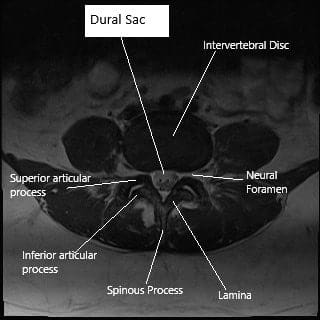

Before commencing the procedure, it is recommended to inspect the surrounding structures (including medial, lateral, anterior, and posterior relations) to identify the anatomy. Accurate understanding of anatomy is crucial because in many instances only a fraction of a structure can be observed. A neuronavigation system can be beneficial, particularly in cases where landmarks are not clearly visible, as in cases of redo surgery.